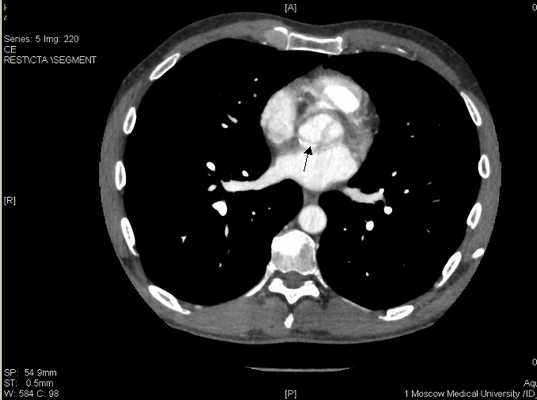

Поскольку от предложенной коронароангиографии пациент вновь отказался, была проведена мультиспиральная компьютерная томография коронарных артерий с контрастированием, которая продемонстрировала протяженный стеноз передней межжелудочковой артерии и окклюзию правой коронарной артерии

Рисунок 11. Стенозирующий атеросклероз коронарных артерий у больного К., 53 лет.

ПМЖВ в проксимальном сегменте имеет кальцинированную протяженную бляшку со стенозированием 50-75% (Указано стрелкой

![ibs11.jpg]()

ПКА в проксимальном сегменте окклюзирована (указано стрелкой), дистальный отдел и ЗМЖВ заполняются контрастным веществом.

![ibs11b.jpg]()